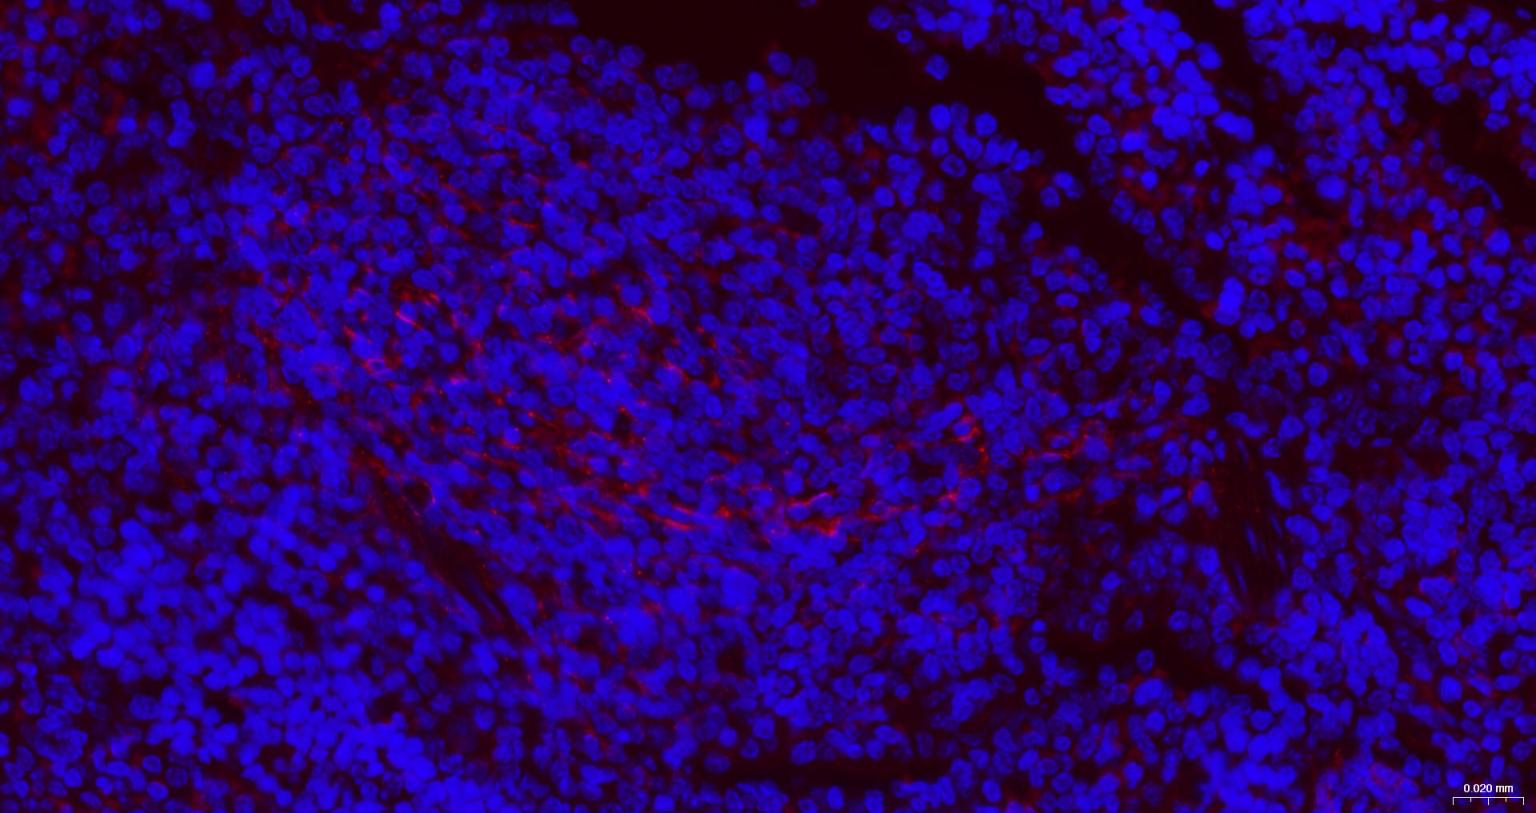

IHC-PHuman, Mouse, Rat1:100-500

IHC-FHuman, Mouse, Rat1:100-500

IFHuman, Mouse, Rat1:100-500

ICC/IFRatHuman, Mouse1:50-200